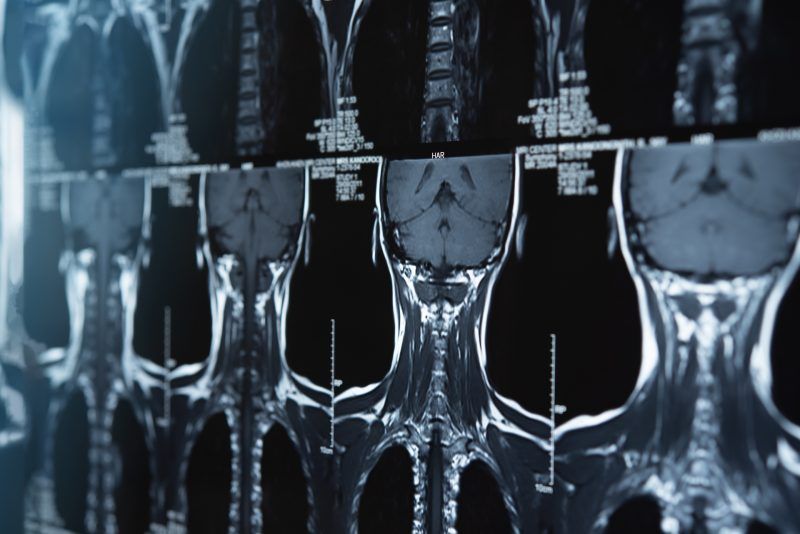

Resonancia magnética de columna cervical: ¿Qué detecta?

La resonancia magnética de la columna cervical es un estudio preciso y seguro. Además, permite diagnosticar problemas neurológicos y ...